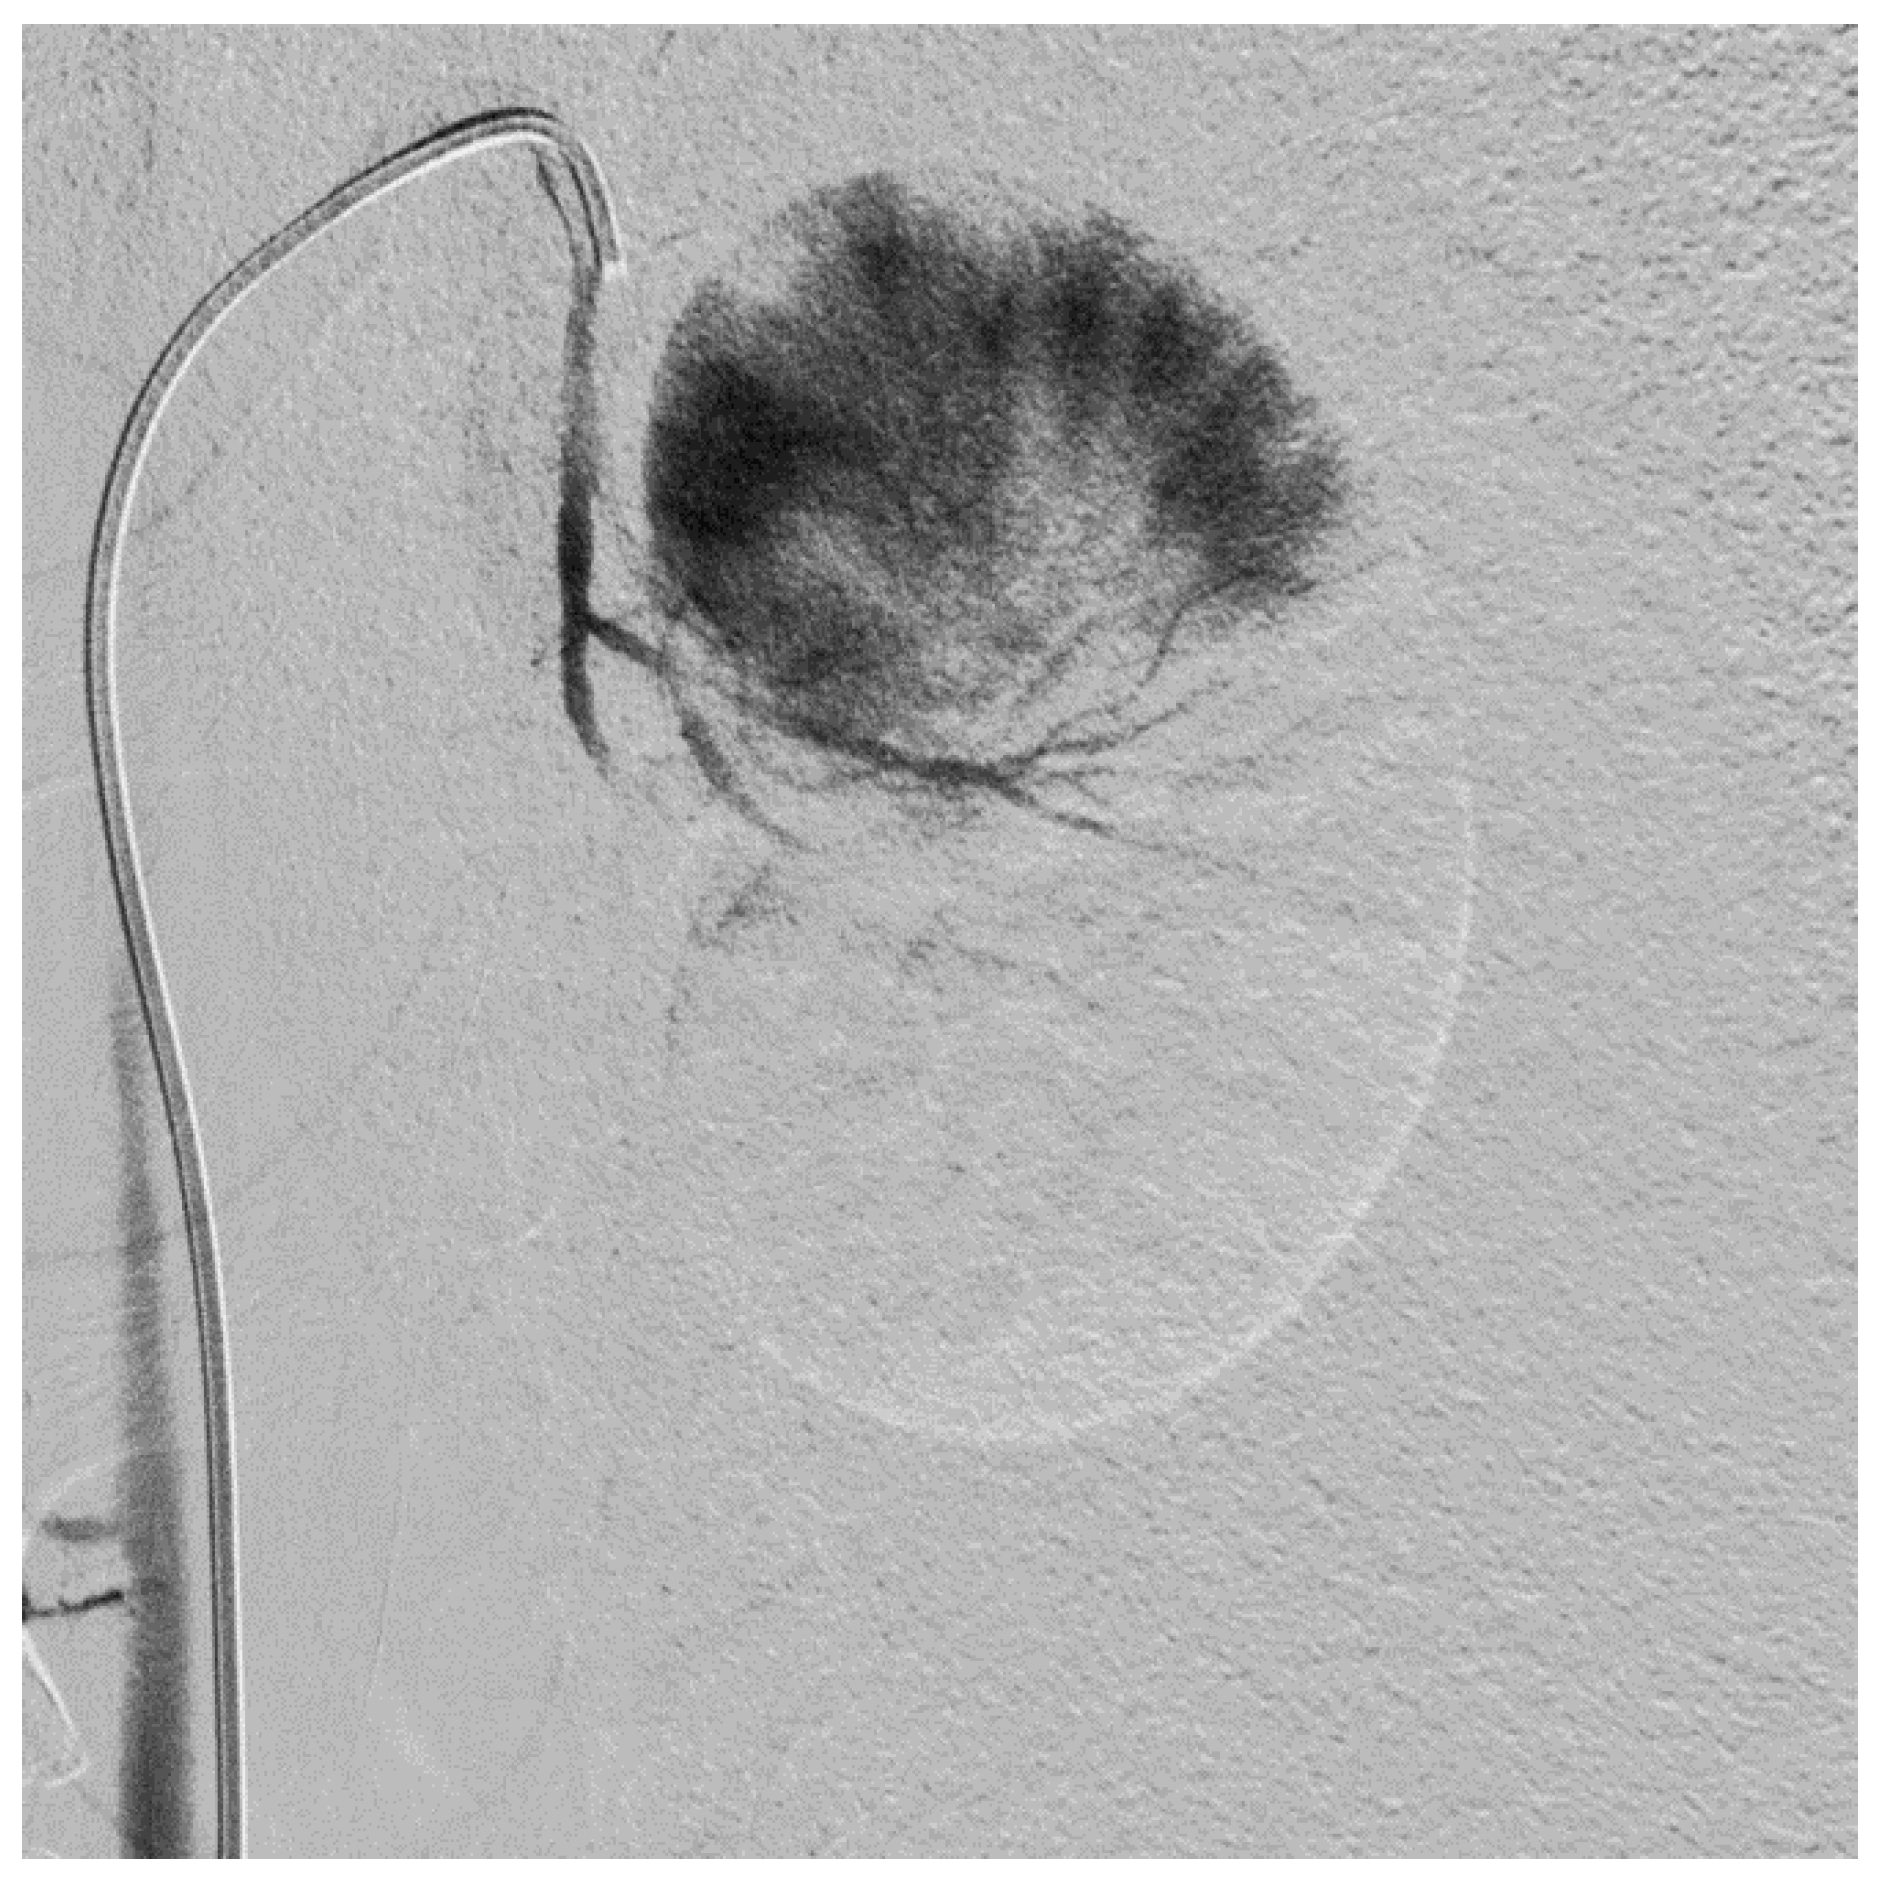

2.2. Subtotal Renal Artery Embolization

3.1. Subtotal Renal Artery Embolization